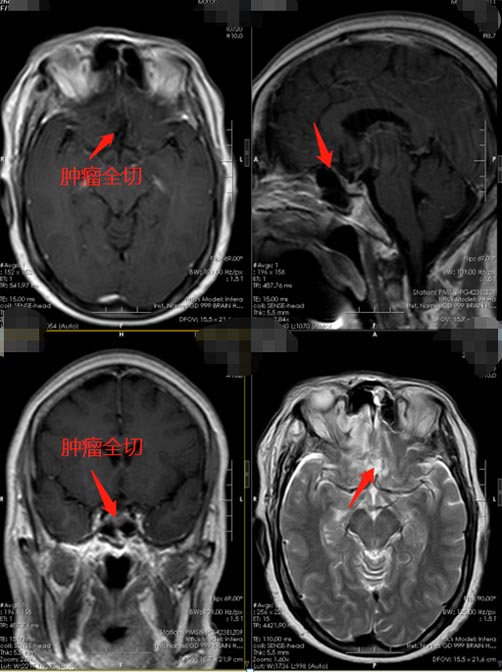

医院副院长、神经外五科主任鲁明在充分了解患者的病情后,决定选择微创:经右侧眉弓入路行前颅窝底脑膜瘤切除术。微创手术是利用锁孔一样大小的骨窗来代替过去大切口、大骨窗,进行颅内的病变切除,具有对患者心理影响小、开关颅时间短、对脑组织牵拉小、减少了无效开颅等优势,以更小的切口、更少的出血、更少的神经功能损伤、更快的术后恢复,使患者获得最大的收益。

术中导航定位肿瘤后,于右侧眉弓中外2/3横切口,长约5cm,见肿瘤包裹双侧前动脉,大约2cm×2×cm1.5cm,予以仔细剥离,保护神经,肿瘤被分块完全切除。术后恢复顺利,第二天周阿姨即可下床活动,第四天办理了出院。病理诊断:脑膜瘤。